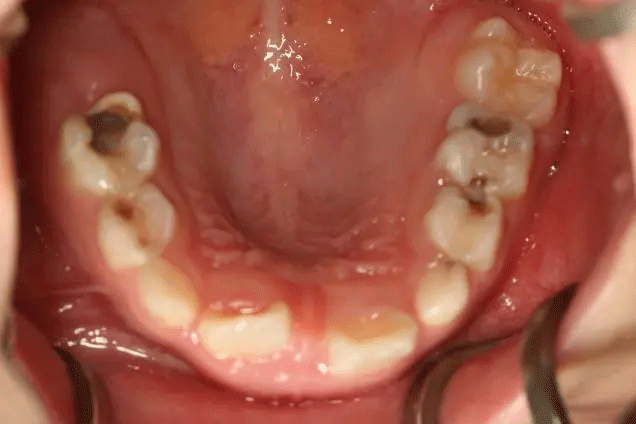

在門(mén)診中發(fā)現(xiàn)

來(lái)口腔科檢查的孩子

有些牙齒都已經(jīng)爛得很嚴(yán)重了

甚至牙齒幾乎都爛光僅剩下牙根